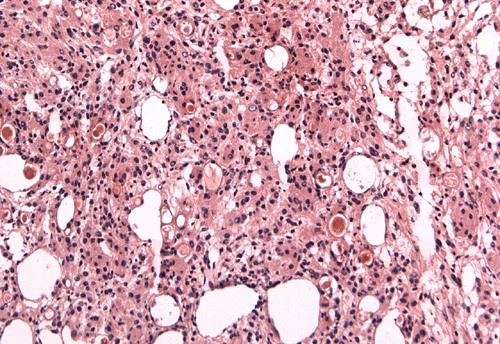

On cytologic preparation, there are irregular clusters of cells and in between these clusters are many single cells (Panel F). The background is clean and if free of mitosis. On high-magnification, some of these cells are arranged in small concentric whorls (ß in Panel G). Pseudonuclear inclusion can be seen in some nuclei (ß in Panel G). The cytoplasm of these cells seems to be triangular, pointy, well defined and finely granular. Quite some clusters of cells with gigantic "bubbles " several times the size of the nucleus containing eosinophilic cores with a halo are present (Panel H). On frozen section, the tumor cells arrange in solid sheets with many microcysts in between. Many of the smaller microcysts contain a eosinophilic, amorphous core that correspond to the giant "bubbles" on the cytologic preparation (Panel I). On high-magnification, the cells have epithelioid appearance with pseudonuclear inclusion in many nuclei (Panel J). These features are highly suggestive of a secretary meningioma. The main differential diagnosis in this case is metastatic adenocarcinoma. Although the gigantic "bubbles" suggest mucin secretory adenocarcinoma, the cytoplasmic vacuoles rare approach the size of several times that of the nuclei as illustrated in this case. Besides, necrosis is often present in metastatic adenocarcinoma.  [Click here to see a mucin producing adenocarcinoma in cytologic preparation] [Click here to compare the cytologic preparation of a metastatic renal cell carcinoma] The large amount of edema on MRI also raises the suspicion of metastatic adenocarcinoma. It should be noted that secretory meningiomas are typically associated with a disproportionally extensive edema.

Histologic findings on  formalin fixed, paraffin sections of the specimen are very similar to that of the frozen sections (Panel K and L). The pseudonuclear inclusions are much better visualized in the paraffin section (Panel M). The core material in the microcysts is strongly PAS positive (Panel N). The tumor cells are focally positive for cytokeratin AE1/AE3 (Panel O) and positive for epithelial membrane antigen (EMA) (Panel P). Also unique to secretory meningioma is focally positive for carcinomembryonic antigen (CEA) (Panel Q).

Macroscopically, secretory meningiomas share common features with other meningiomas. It  often occurs as globular discrete mass with a dural base attachment ("dural based tumor"). Color and consistency depend on the components of the tumor: As the vascularity increase, the tumor tends to change from tan to red; as fibroblast and calcification increase, it is become tough, may be gritty. Microscopically, the hallmark is the presence of focal epithelioid proliferation, in the form of intracellular eosinophilic PAS-positive diastase resistance secretory material. These bodies are know as pseudopsammoma bodies as illustrated in this case. These pseudopsammoma have a clear halo about their eosinophilic noncalcified core 7. Similar to other meningiomas, tumor cells in meningothelial arrangement are usually present and cellular whorls are also seen. Pseudonuclear inclusion (intranuclear cytoplasmic invainations) are often found in the nuclei. [Click here to see a meningothelial meningioma]

Immunohistochemically, the intracellular pseudopsammoma bodies and surrounding cells are reactive to epithelial membrane antigen (EMA), cytokeratin (CK7), and carbohydrate antigen 19-9, in decreasing frequency. The reactivity to CK20 is negative 2, 6  Also unique to secretory meningioma is the expression of carcinoembryonic antigen (CEA) that is often present around the pseudopsammoma bodies. Probst-Cousin et al., demonstrated a mean MIB-1 labeling index  of 3.8%. Ultrastructurally, the pseudopsammoma bodies consist of spaces lined by microvilli and filled with contents that are variably amorphous, particulate, lamellar, or vesicular.